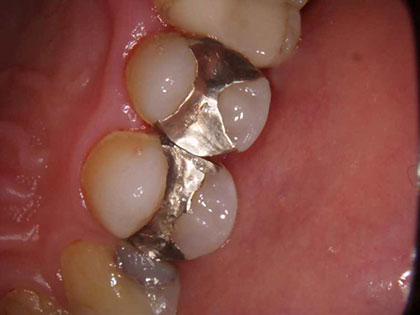

金属の詰め物を白くしたいとの事で来院された患者様の症例になります

初診時の写真がこちら

治療完了時の

写真がこちら

症例

20代女性

主訴

金属の詰め物を白くしたい

治療回数

2回

治療内容

emaxインレー

治療費用

50,000円(税抜)

リスク・

副作用

一次的にしみたりします。割れたり、欠ける可能性があります。

治療費用内訳

(合計:50,000円)

emaxインレー:

50,000円